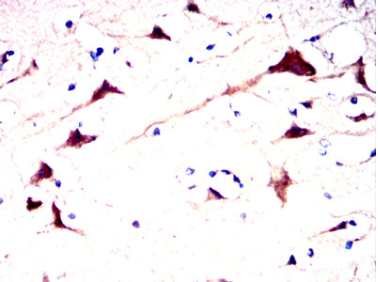

AFP Mouse Monoclonal antibody[2G4H3]

Immunogen :   Purified recombinant fragment of human AFP (AA: 19-210) expressed in HEK293-6e cells supernatant.

IHC    1/200 - 1/1000